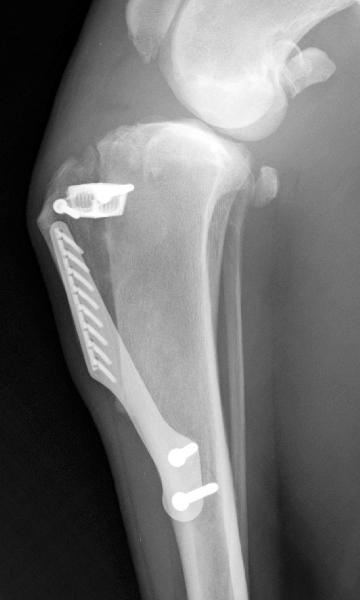

další technické vybavení:kompletní špičkové vybavení pro artroskopii, počítačová tomografie (CT), vybavení pro operace šedého zákalu fakoemulzifikací (Alcon, mikroskop Zeis), C-rameno, 50kW hf stacionární RTG se skiaskopií a digitalizací RTG obrazu, 12 kanálové EKG, diagnostický ultrazvuk s barevným dopplerem, biochemický analyzátor, pětipopulační hematologický analyzátor , analyzátor acidobazické rovnováhy a iontů, kryokauter, kryospray, 5x aparát pro inhalační anestezii - 3x s řízenou ventilací a vestavěným komplexním monitoringem (plyny, NIBP, SpO2), kardiomonitory, monitory dýchacích plynů, dopplerovský monitor srdečního výdeje, kapnooxymetry, flexibilní endoskopy (gastro, broncho...), rigidní endoskopy, ultrazvuk na zubní kámen, kompletní stomatologické vybavení (vrtačky, polymerizační lampa...),čipování a mnoho dalšího (viz: www.azvet.cz) |

zaměření:Kromě všeobecné veterinární péče sloužíme také jako referenční klinika pro chirurgii, ortopedii včetně artroskopie, vyšetření ultrazvukem včetně echokardiografie, chirurgii šedého zákalu, kryochirurgii, stomatologii, cytologická vyšetření. servis pro chovatele:pořádání vzdělávacích akcí (přednášky, semináře) servis pro kolegy:artroskopie, laparoskopie, ortopedie (vyšetření i operace - TTA, TPLO, CWO, TPO, DPO, DARtroplastika, JPS aj.), složitější chirurgické zákroky (i v řízené inhalační anestezii), operace katarakty fakoemulzifikací s implantací, kryochirurgie (především ošetření novotvarů GCA, distichiázy, ektop. cilií a některých neoperabilních nádorů), složitější RTG vyšetření, skiaskopie, angiografie, flexibilní endoskopie - především gastroskopie a kolonoskopie včetně histologického vyšetření, rhinoskopie a tracheo-bronchoskopie, statim vyšetření krve (biochemie, hematologie), stomatologie -záchovná, protetika i ortodoncie, vyšetření ultrazvukem vč. echokardiografie a biopsií orgánů pod kontrolou USG |